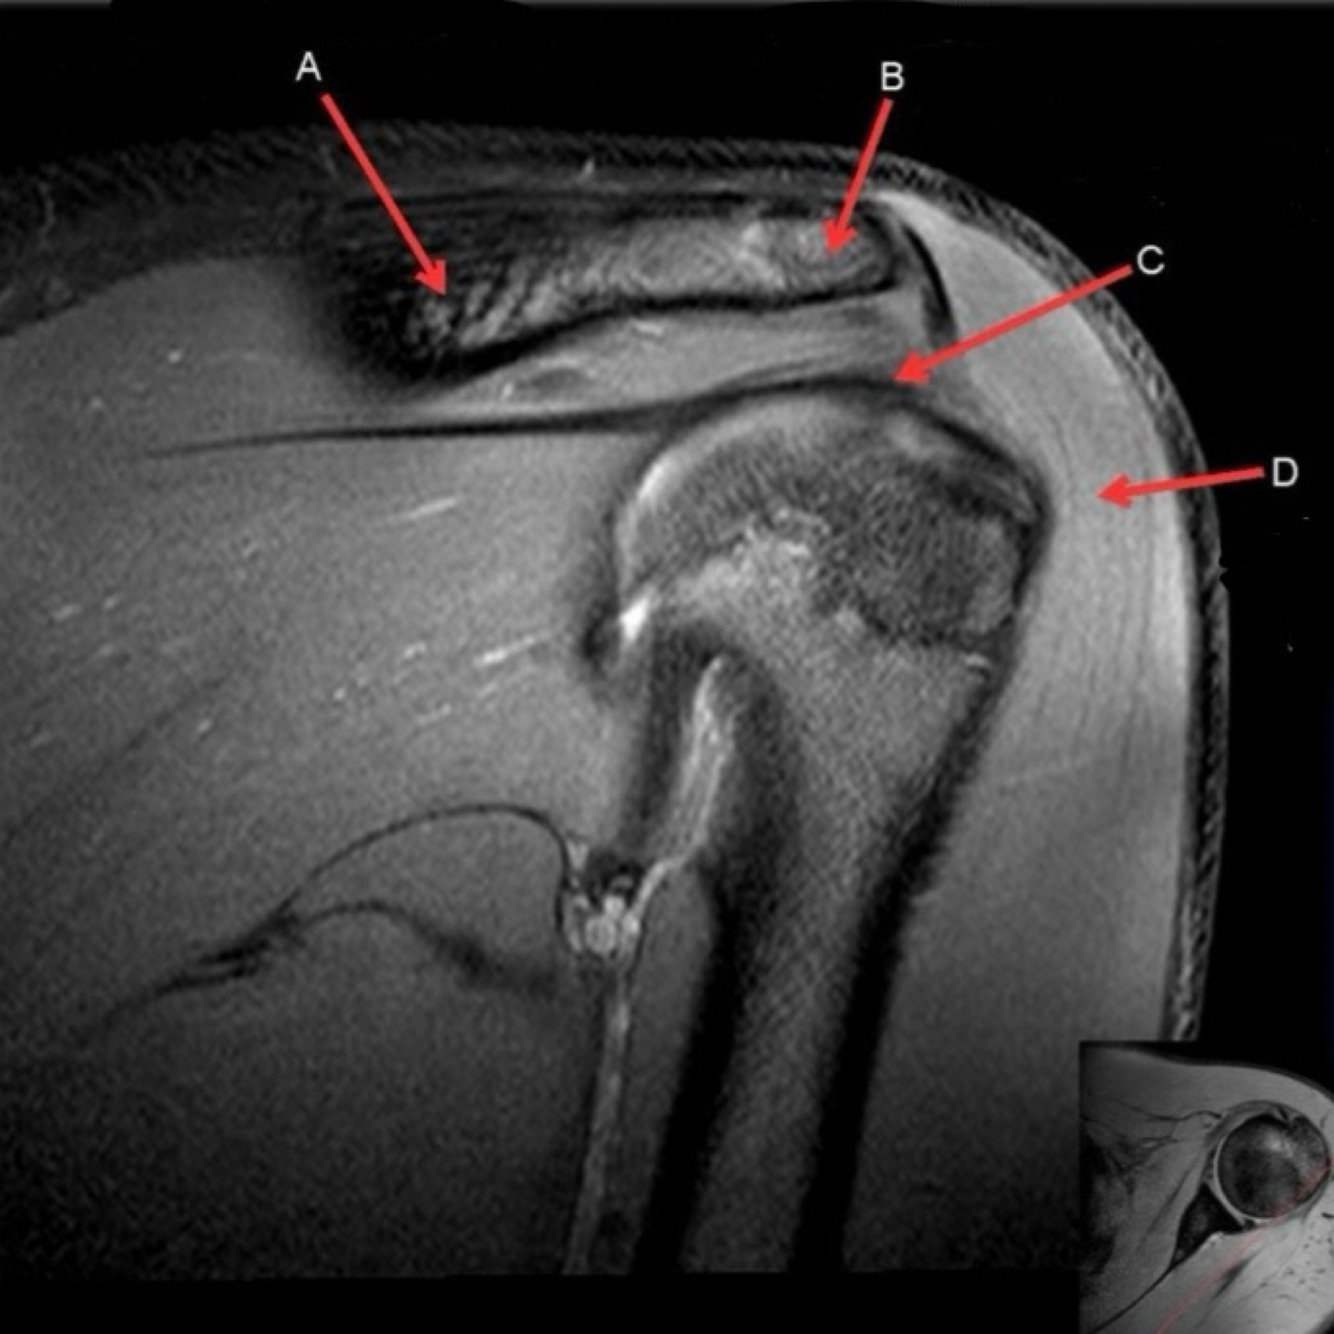

11

Q

What is letter A?

A

ANTERIOR LABRUM

12

What is letter B?

BICEPS TENDON (LONG HEAD)

How well did you know this?

13

What is letter C?

HEAD OF HUMERUS

14

What is letter D?

POSTERIOR LABRUM